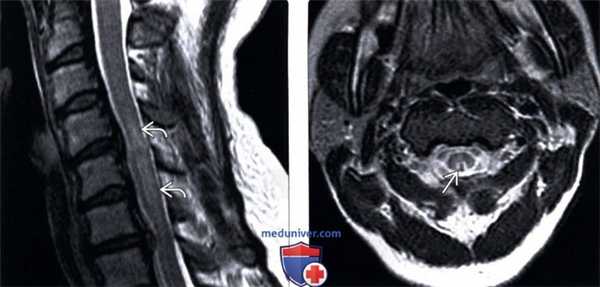

(Слева) Рентгенография в боковой проекции: типичные признаки отека заглоточного пространства на фоне стрептококкового фарингита. Синдром Гризеля может развиться на любой стадии инфекционного заболевания - от отека клетчатки до распространенного абсцедирования.

(Справа) Аксиальный КТ-срез с КУ: абсцесс заглоточного пространства, развившийся на фоне левостороннего тонзиллита. Признаков поражения С1-С2 сочленения в данном случае не видно, однако становится понятным, насколько легко воспалительный процесс может перейти и сюда. (Слева) Сагиттальный срез, STIR МР-И: случай септического поражения краниовертебрального сочленения, характеризующегося выраженным усилением сигнала превертебрального пространства В, зубовидного отростка и стиранием границ передней дуги С1. Такая картина достаточно сильно отличается от менее агрессивных проявлений синдрома Гризеля.

(Справа) Аксиальный срез, Т1-ВИ с КУ: признаки инфекционного поражения краниовертебрального сочленения и формирования множественных мелких абсцессов в задних отделах носоглотки В. Обратите внимание на тесное взаиморасположение носоглотки и атлантоаксиального сочленения, что обусловливает возможность распространение сюда инфекции из носоглотки.